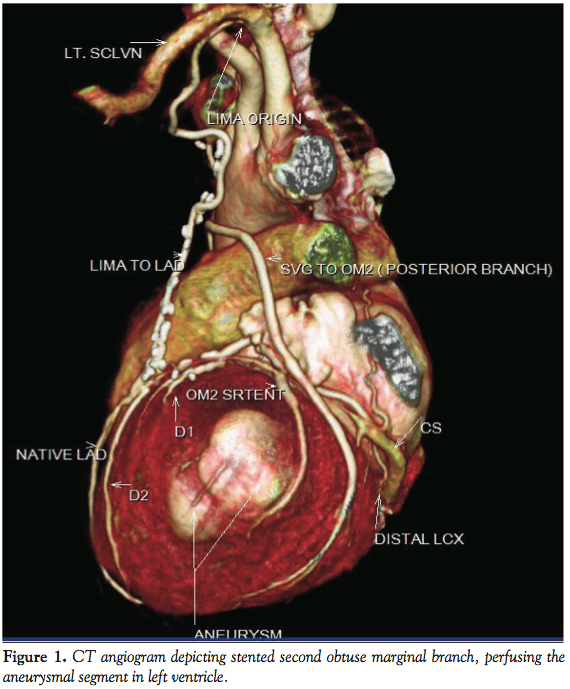

Case Report. A 65-year-old male patient presented with dyspnea on minimal exertion, New York Heart Association (NYHA) class III from 4 months. He was a known hypertensive, non-diabetic and suffered anterior wall myocardial infarction in 1998. Coronary angiography showed double vessel disease in 1998 [left anterior descending coronary artery (LAD) mid 100% stenosis and second obtuse marginal (OM2) 95%]. Subsequently patient underwent coronary artery bypass grafting with a left internal mammary artery graft to the LAD and saphenous venous graft to OM2. In 2007 he developed unstable angina and underwent percutaneous transluminal coronary angioplasty with stent to native OM2. Two-dimensional echocardiogram showed regional wall motion abnormality in LAD and left circumflex coronary artery territory with left ventricle (LV) ejection fraction of 25% with LV aneurysm in lateral wall. Now with complaints of dyspnea on exertion NYHA 2, he was again taken up for coronary angiogram that showed mid LAD 100% stenosis, mild plaquing in right coronary artery, and left circumflex coronary artery showed distal 50% plaque with patent stent in OM2 and complete occlusion of OM2 branch that was grafted in 1998. There was a coronary artery fistula distally in OM2 draining to LV aneurysm (Figure 1). Stress thallium was done that showed non-significant reversible myocardial ischemic deficit in LAD territory. Patient was advised medical management as this fistula was unlikely to result in significant myocardial overload to justify percutaneous closure. Review of older angiograms did not show its presence until 2007 from most recent angiogram. CT angiogram clearly showed a fistula arising from OM2 and draining into LV aneurysm in the lateral wall (Figure 2).